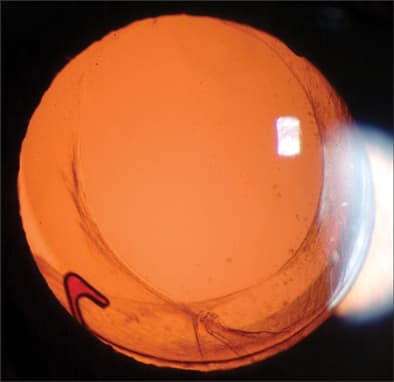

Retinal physicians are usually involved in the management of endophthalmitis associated with cataract surgery (Figure 1). It has been estimated that the risk of endophthalmitis following cataract surgery is approximately 1 in 1000. Since there are over 2 million cataract operations per year performed in the United States,1 the magnitude of this problem is significant. Current management of endophthalmitis after cataract surgery is based largely on data provided by the Endophthalmitis Vitrectomy Study (EVS), a multicenter clinical trial sponsored by the National Eye Institute that compared immediate pars plana vitrectomy (PPV) to immediate vitreous tap, and intravenous antibiotics to no intravenous antibiotics, for the treatment of acute-onset (within 6 weeks) endophthalmitis following cataract surgery or secondary intraocular lens (IOL) implantation.2,3

Figure 1. Acute-onset endophthalmitis following clear corneal cataract surgery.